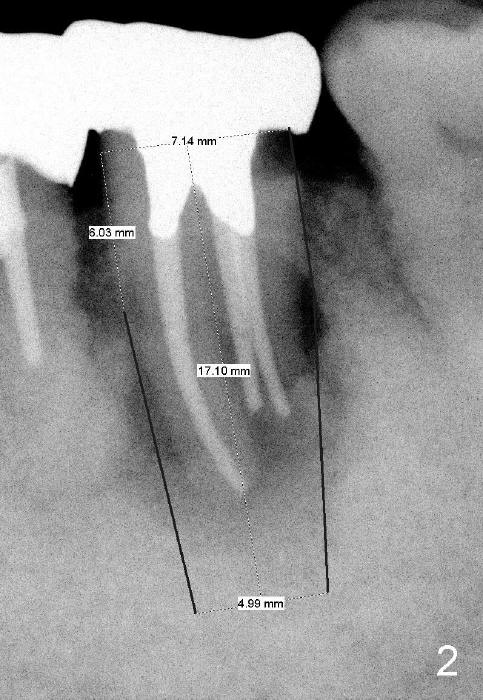

A 84-year-old man has severe pain distal to #18 (Fig.1). The affected tooth is planned to be restored by a 7x17 mm implant (Fig.2).